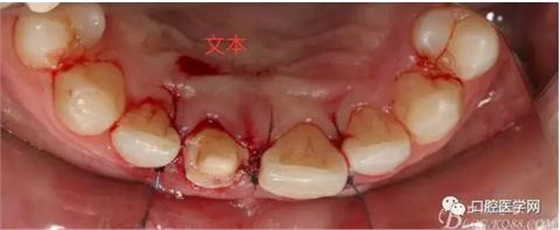

翻瓣 見(jiàn)11釉牙骨質(zhì)界存在,牙槽嵴頂?shù)接匝拦琴|(zhì)界不足2mm。21牙槽嵴頂?shù)接匝拦琴|(zhì)界不足2mm

去骨后,牙槽嵴頂?shù)接匝拦琴|(zhì)界達(dá)到2.5mm。保留11,21之間的牙槽嵴頂,不改變齦乳頭的狀態(tài)。